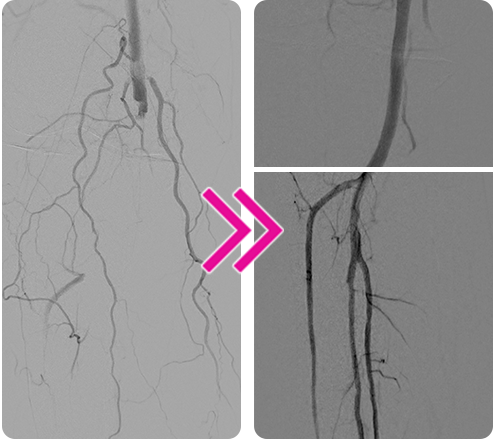

Removal of Mixed-Morphology, Multivessel Lower Extremity Clot With 3 Passes of the Pounce™ Thrombectomy System

Jay Mohan, DO, FACC, FSCAI, FASE, RPVI

A woman in her early 80s presented with approximately 2 weeks of right lower extremity pain with numbness and tingling. Patient history included severe peripheral artery disease, a history of left femoral stent placement, and atrial fibrillation. The patient had been taken off apixaban due to hemorrhoidal bleeding.